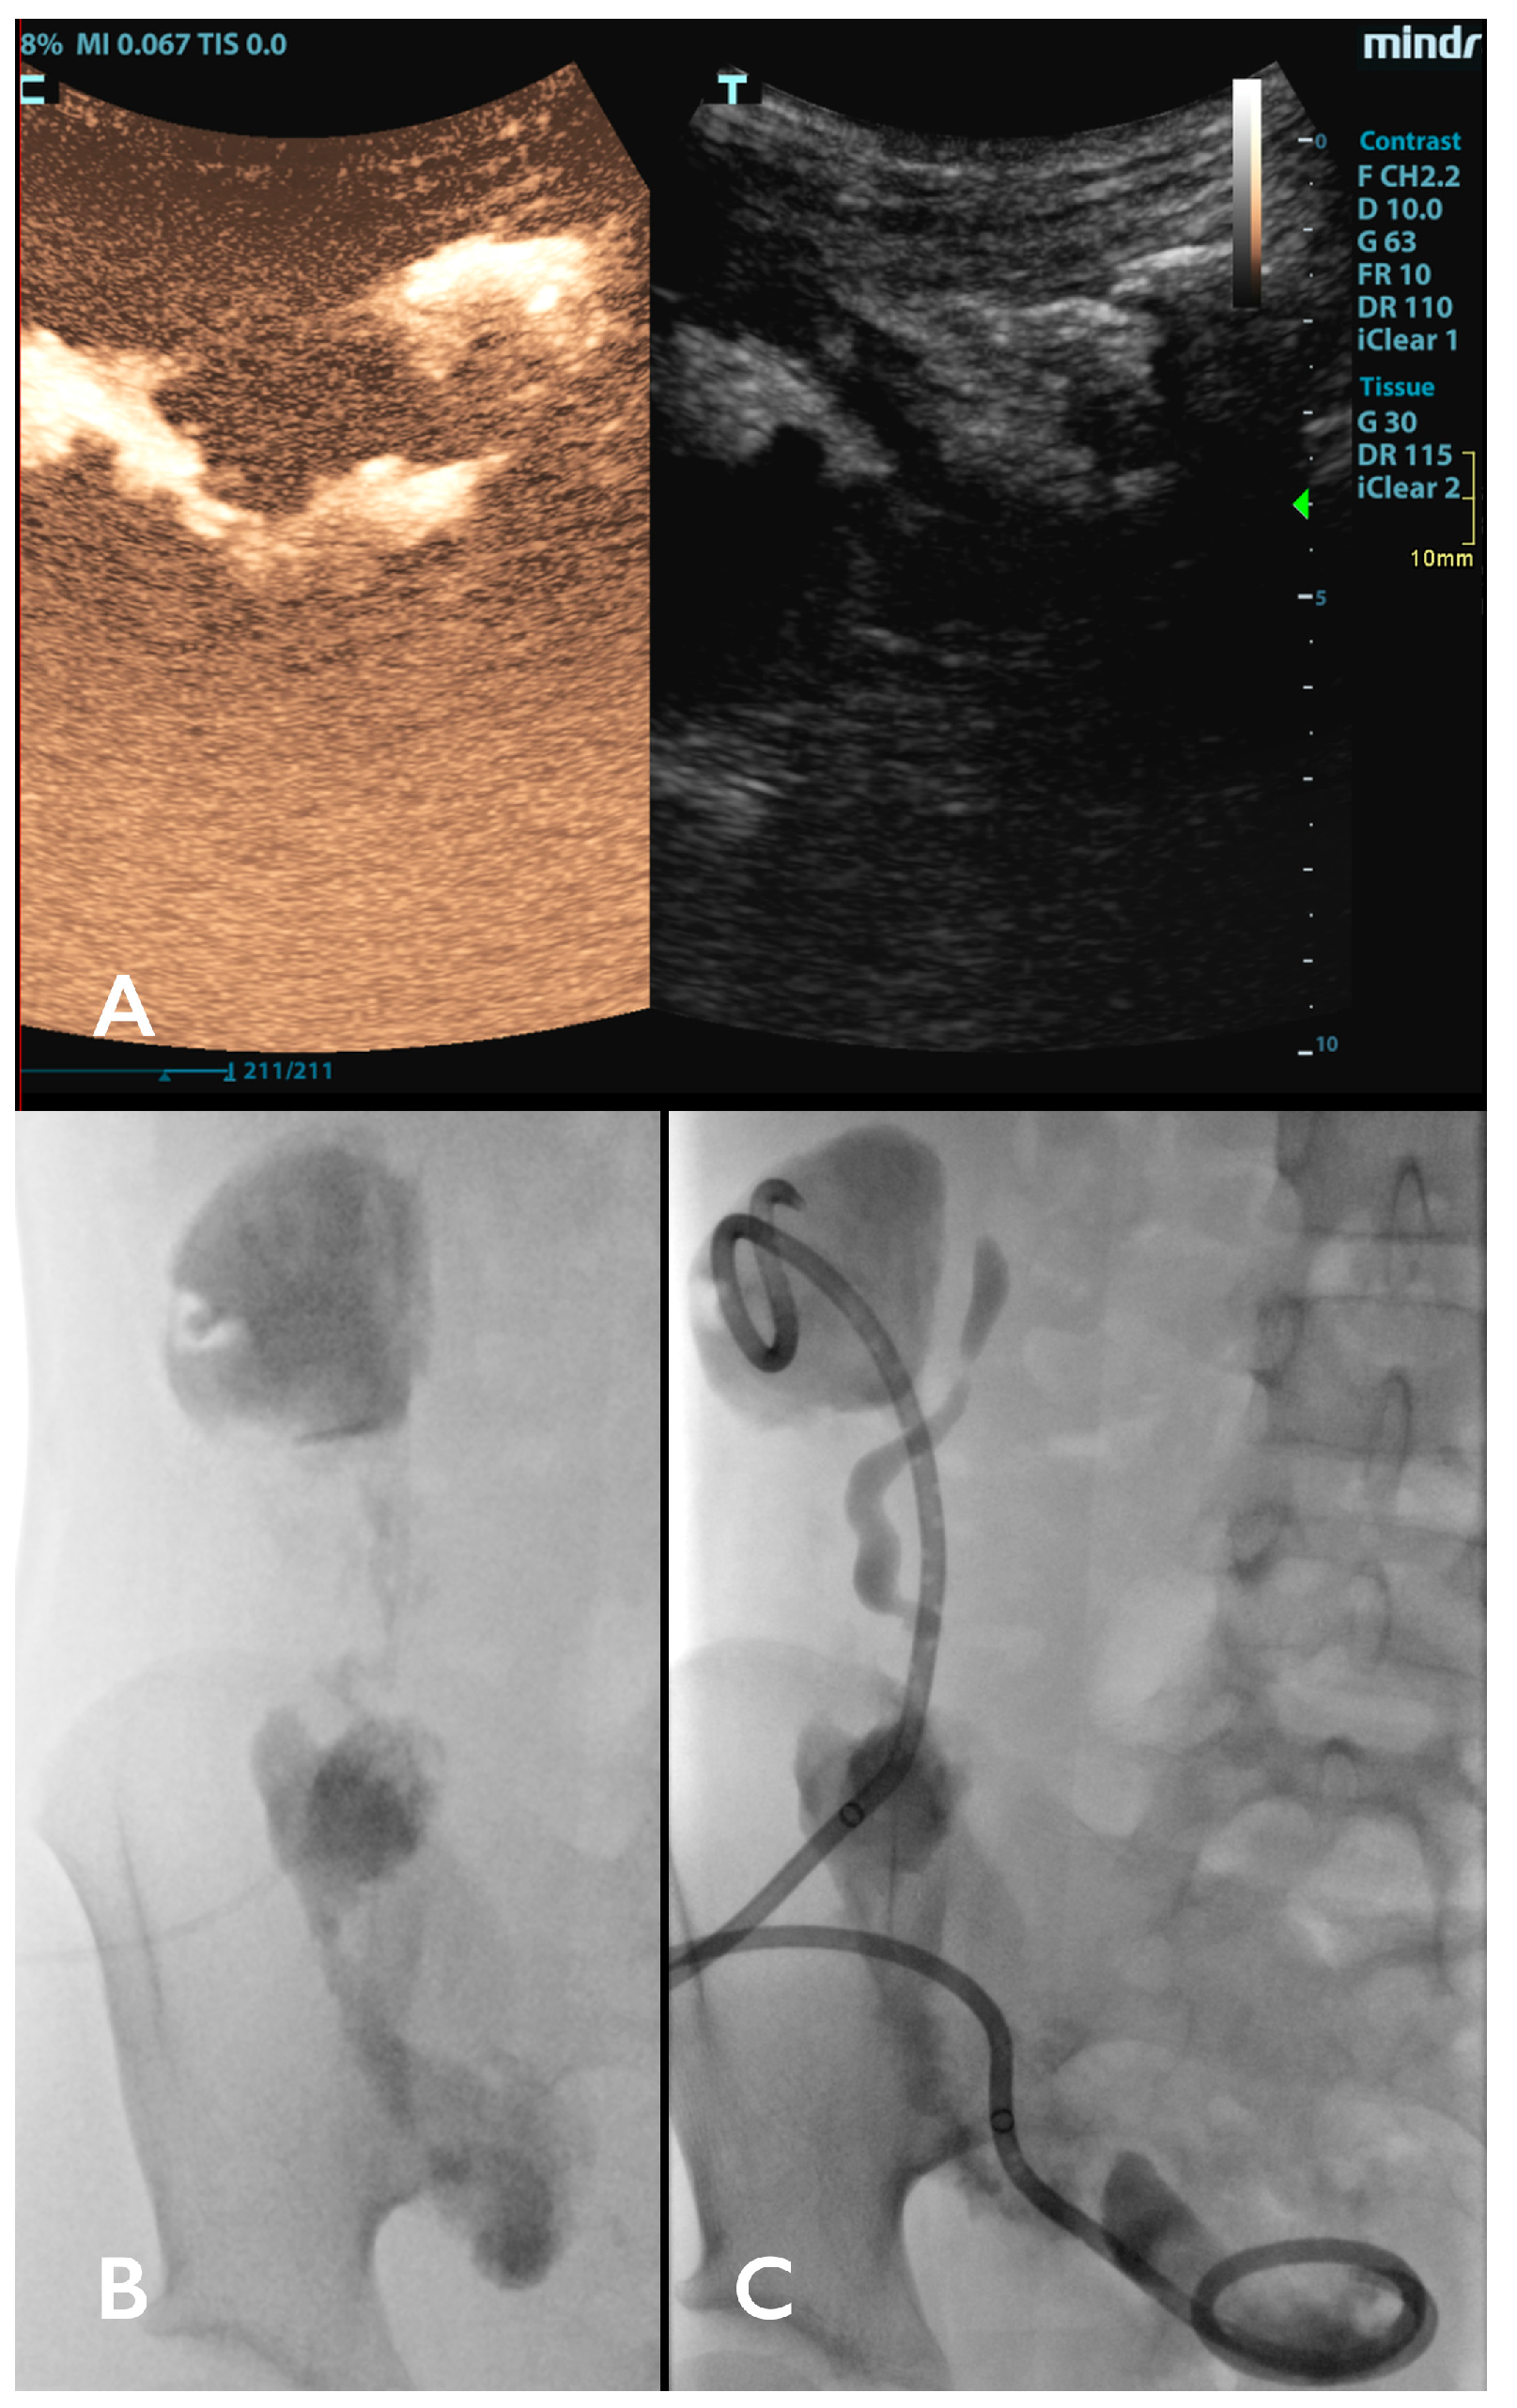

- Huang, D.Y.; Yusuf, G.T.; Daneshi, M.; Ramnarine, R.; Deganello, A.; Sellars, M.E.; Sidhu, P.S. Contrast-Enhanced Ultrasound (CEUS) in Abdominal Intervention. Abdom. Radiol. 2018, 43, 960–976. [Google Scholar] [CrossRef] [PubMed]

- Meloni, M.F.; Andreano, A.; Laeseke, P.F.; Lee, F.T.; Sironi, S.; Filice, C.; Ferraioli, G. Contrast-Enhanced Ultrasonographic Findings in a Brucellar Hepatic Abscess. J. Ultrasound Med. 2008, 27, 1511–1515. [Google Scholar] [CrossRef] [PubMed][Green Version]

- Kishina, M.; Koda, M.; Tokunaga, S.; Miyoshi, K.; Fujise, Y.; Kato, J.; Matono, T.; Sugihara, T.; Murawaki, Y. Usefulness of Contrast-Enhanced Ultrasound with Sonazoid for Evaluating Liver Abscess in Comparison with Conventional B-Mode Ultrasound. Hepatol. Res. 2015, 45, 337–342. [Google Scholar] [CrossRef] [PubMed]